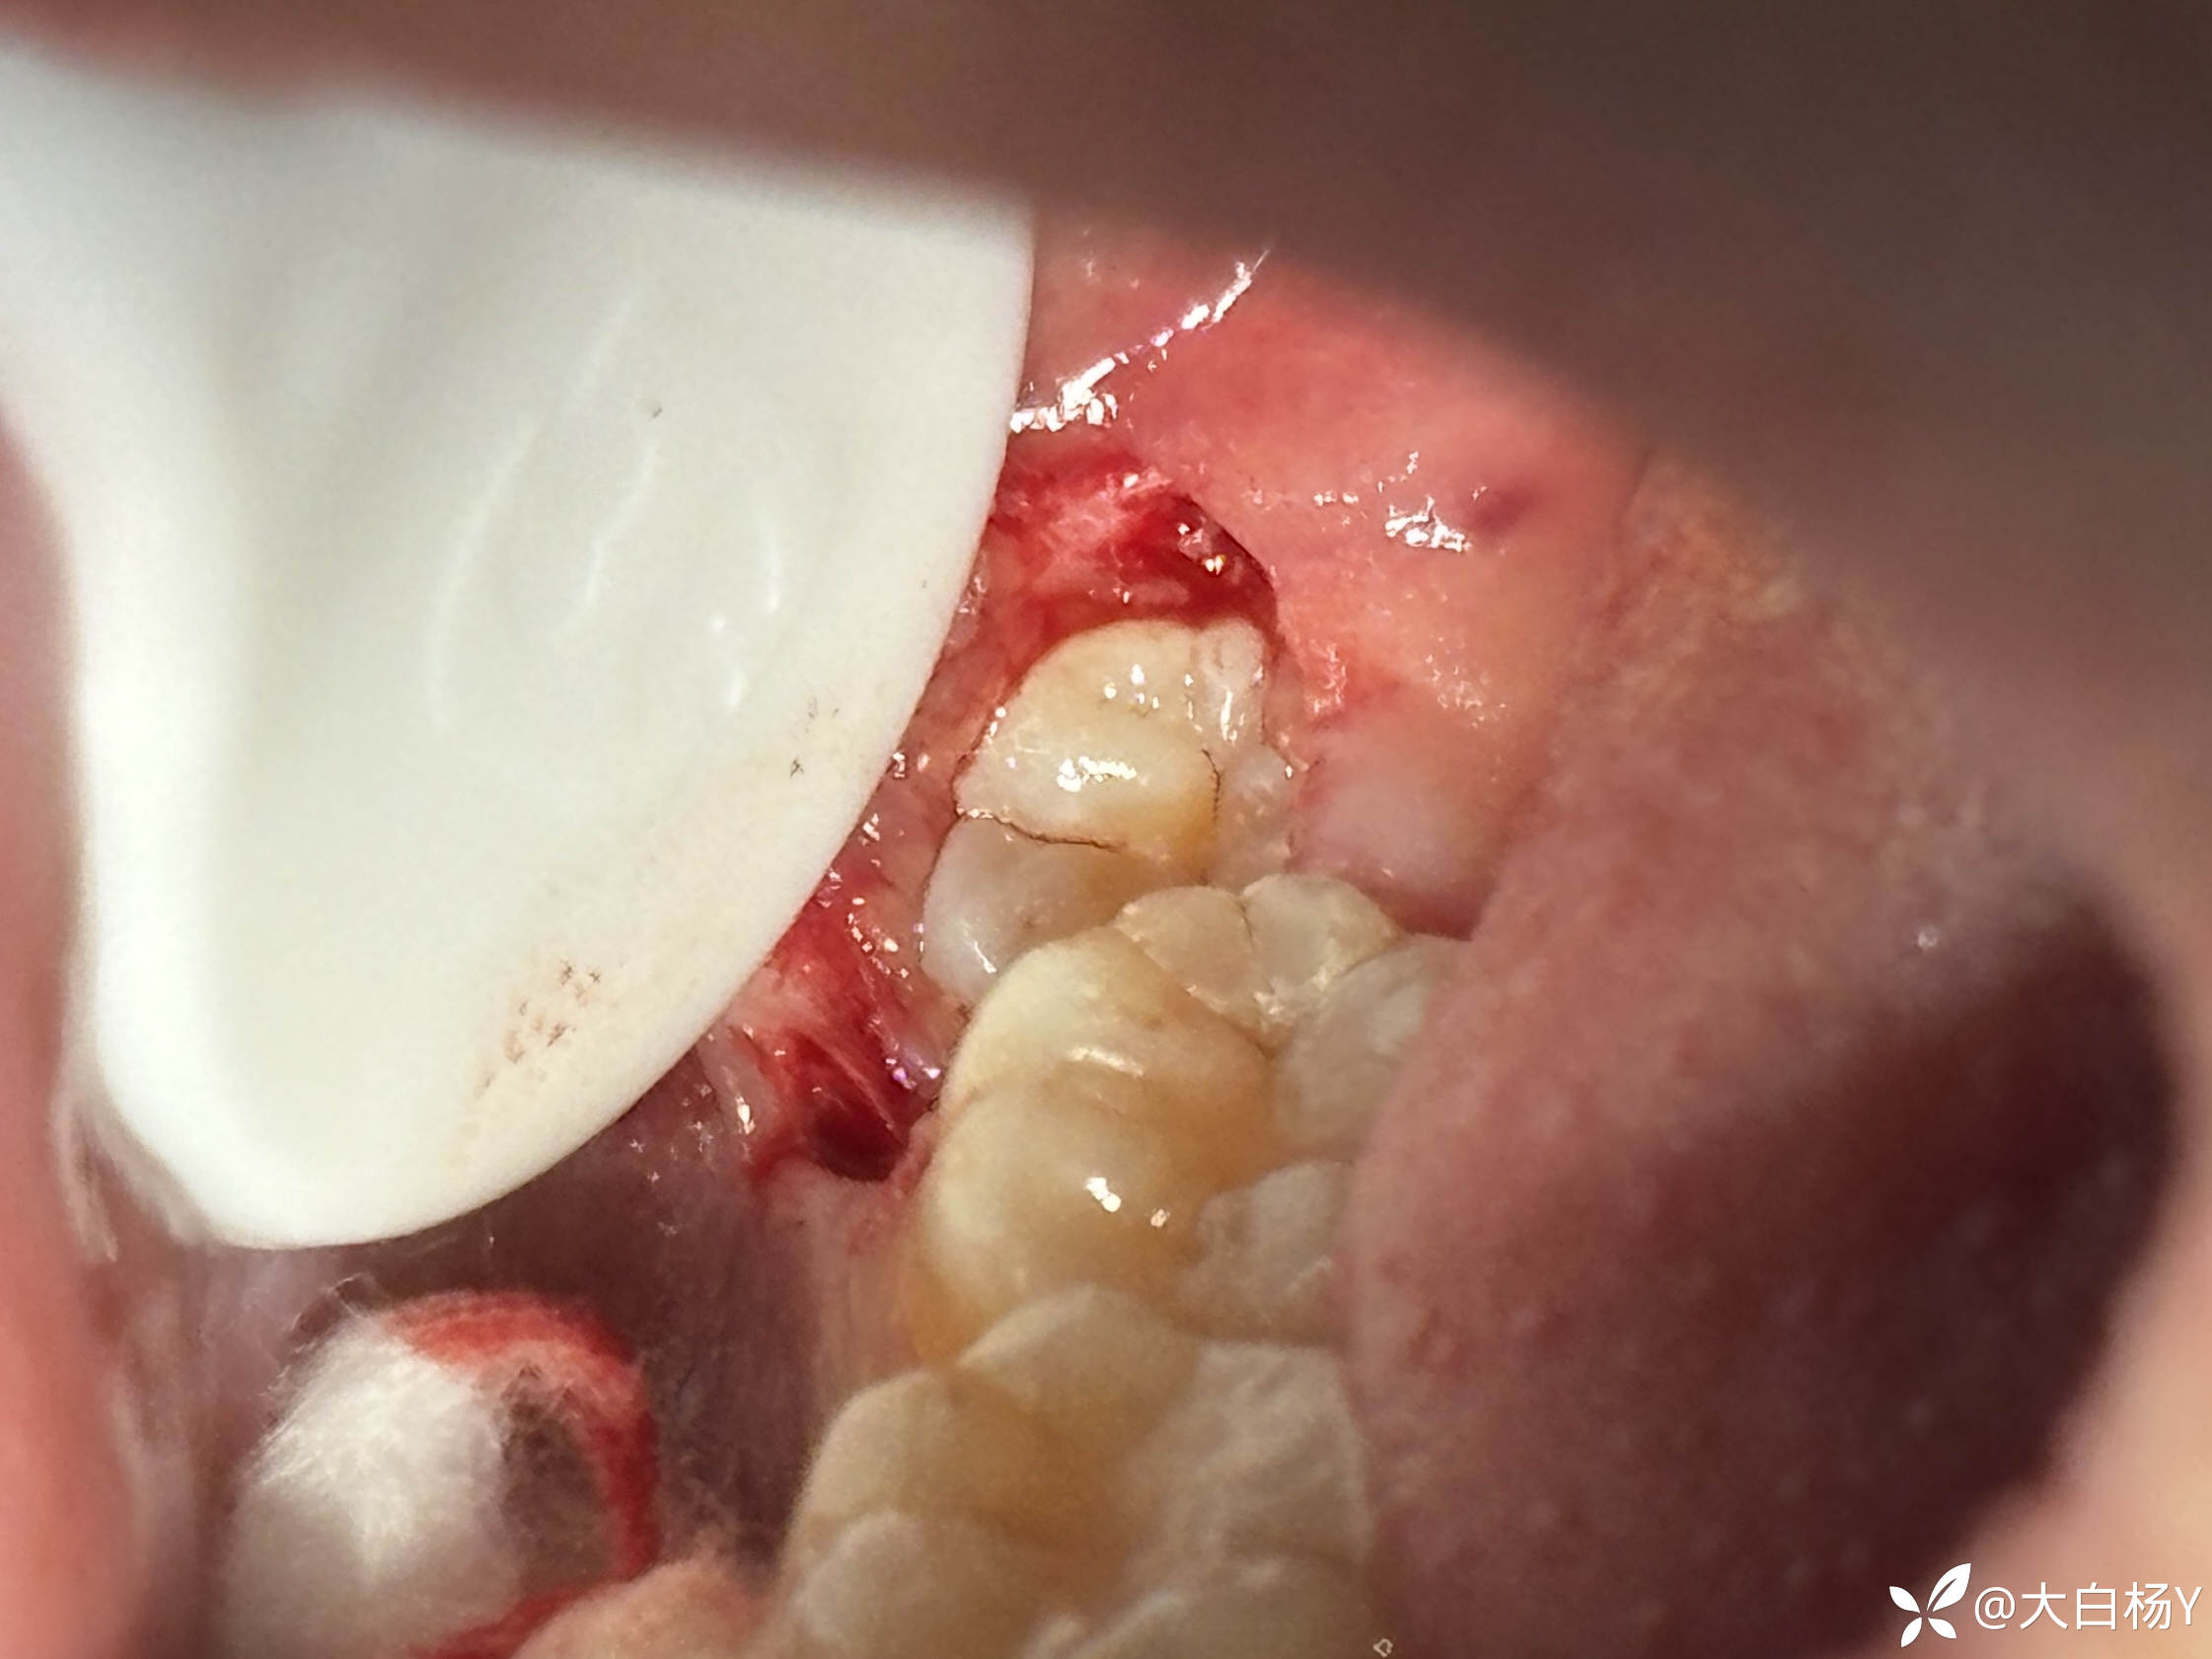

翻瓣:

img